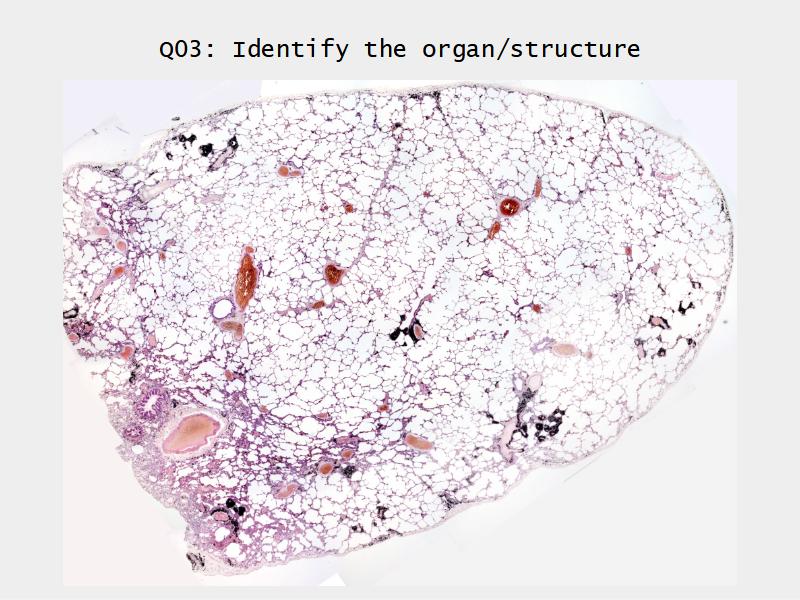

Slides: Respiratory System

- Slide 72 & 74: Lung

Lungs